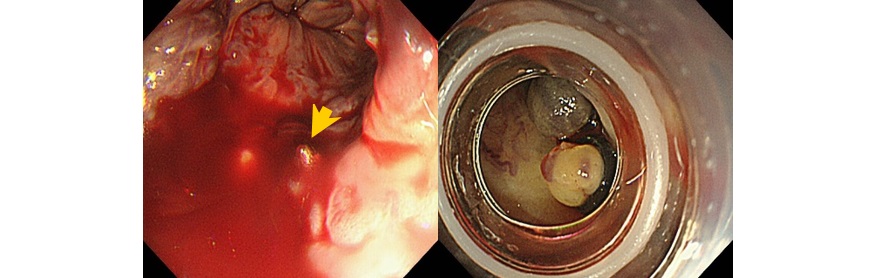

『食道静脈瘤破裂に対する結紮止血術』

大腸ポリープ切除術、早期癌に対する内視鏡的粘膜剥離術、胃潰瘍などからの出血に対する内視鏡的止血術、食道静脈瘤からの出血に対する結紮術、アニサキス(寄生虫)や薬パッケージの誤飲に対する異物摘出術など。また胆道・膵臓系では、内視鏡を用いた胆石除去や、胆道感染や癌に伴う黄疸に対する内視鏡的な減黄術(ステント留置術)など各種行っております。